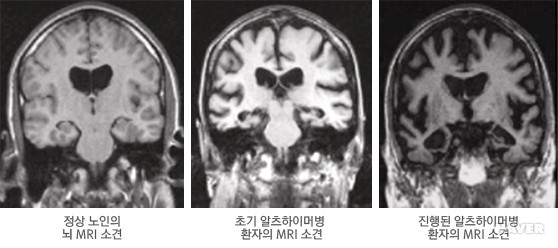

5. 뇌 영상검사

뇌 영상검사는 자기공명영상(MRI), 컴퓨터단층촬영(CT) 등 구조적 뇌 영상검사와 양자방출단층촬영(PET), 단일광자방출촬영(SPECT) 등 기능적 뇌 영상검사로 구분된다. MRICT는 뇌의 구조나 모양을 살펴보기 위한 검사로 알츠하이머병에서 나타나는 뇌의 위축, 뇌실 확대 등 뇌의 구조적 이상 소견을 확인할 수 있다. 근래에는 CT보다 해상도가 높은 MRI를 널리 사용한다. 알츠하이머병에서는 MRI 검사상 특징적인 내측두엽 위축 소견이 비교적 초기 단계에서부터 확인되는 경우가 흔하다.

알츠하이머병 MRI 영상